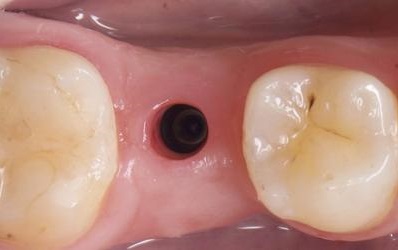

trụ phục hình giải phẫu cá nhân hóaHình ảnh lỗ lợi và mô nha chu được tạo hình từ trụ lành thương cá nhân hóa: có hình thể giải phẫu giống như mô nha chu trên răng thật.

trụ lành thương sản xuất sẵn

Hình ảnh lỗ lợi được tạo ra từ trụ lành thương sản xuất sẵn: bé, tròn, không giống hình thể giải phẫu.